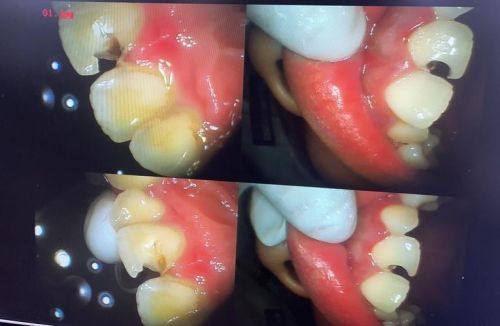

5. 我的牙齿有龋齿,来到安美齿口腔诊所补牙。医生操作特别细致,补完牙后没有任何不适,而且价格合理。这家诊所的环境也特别舒适,让人感觉特别放松,以后看牙还会选择这里。